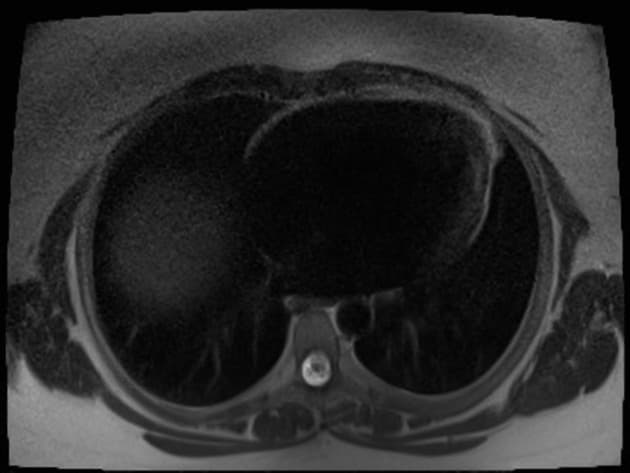

Axial T2

MRI•Axial T2•1 / 24

- Tổn thương dạng thùy (lobulated) kích thước 35 x 45 mm nằm ở phân đoạn V của thuỳ phải, liền kề với túi mật (gallbladder).

- Tổn thương này tăng tín hiệu (hyperintense) trên hình ảnh T2-weighted MRI.